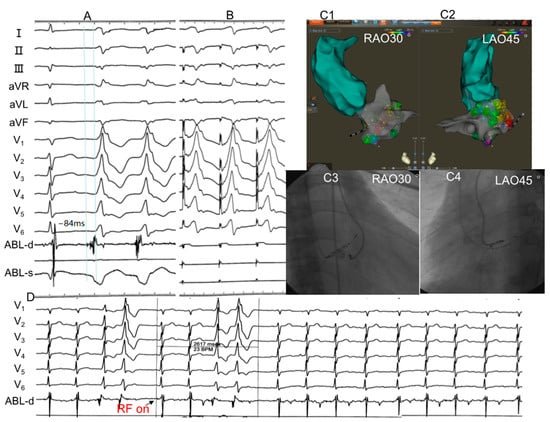

3.2. Electrophysiological Study and Radiofrequency Catheter Ablation

3.6. IDT and MDI Predicted the VAs Arising from the Epicardium

3.7. Q(q)R(r) Morphology in Lead V1 Predicted the VAs Arising from the Endocardial Septal Wall Adjacent to the MA